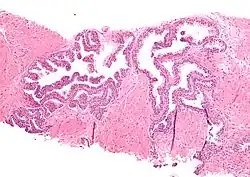

| Micrograph showing high-grade prostatic intraepithelial neoplasia. H&E stain. | |

HGPIN typically has one of four different histologic patterns:[2]

- tufted (fascicular patterning)

- micropapillary,

- cribriform and,

- flat.

Microscopically, PIN is a collection of irregular, atypical epithelial cells. The architecture of the glands and ducts remains normal. The epithelial cells proliferate and crowding results in a pseudo-multilayer appearance. They remain fully contained within a prostate acinus (the berry-shaped termination of a gland, where the secretion is produced) or duct. The latter can be demonstrated with special staining techniques (immunohistochemistry for cytokeratins) to identify the basal cells forming the supporting layer of the acinus. In prostate cancer, the abnormal cells spread beyond the boundaries of the acinus and form clusters without basal cells. In HGPIN, the basal cell layer is disrupted but present. PIN is primarily found in the peripheral zone of the prostate (75-80%), rarely in the transition zone (10-15%) and very rarely in the central zone (5%), a distribution that parallels the zonal distribution for prostate carcinoma.[7]

Several architectural variants of PIN have been described, and many cases have multiple patterns. The main ones are tufting, micropapillary, cribriform, and flat. Although these different appearances may cause confusion with other conditions, they have not been found to be of clinical importance. Rarer types are signet-ring-cell, small-cell-neuroendocrine, mucinous, foamy, inverted, and with squamous differentiation.[3]